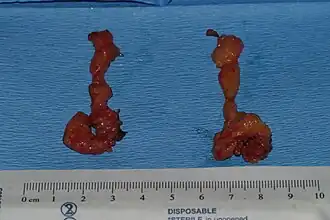

Cheek reduction: The buccal fat pads extracted from a patient who underwent bilateral cheek reduction

Cheek reduction: The buccal fat pads extracted from a patient who underwent bilateral cheek reduction